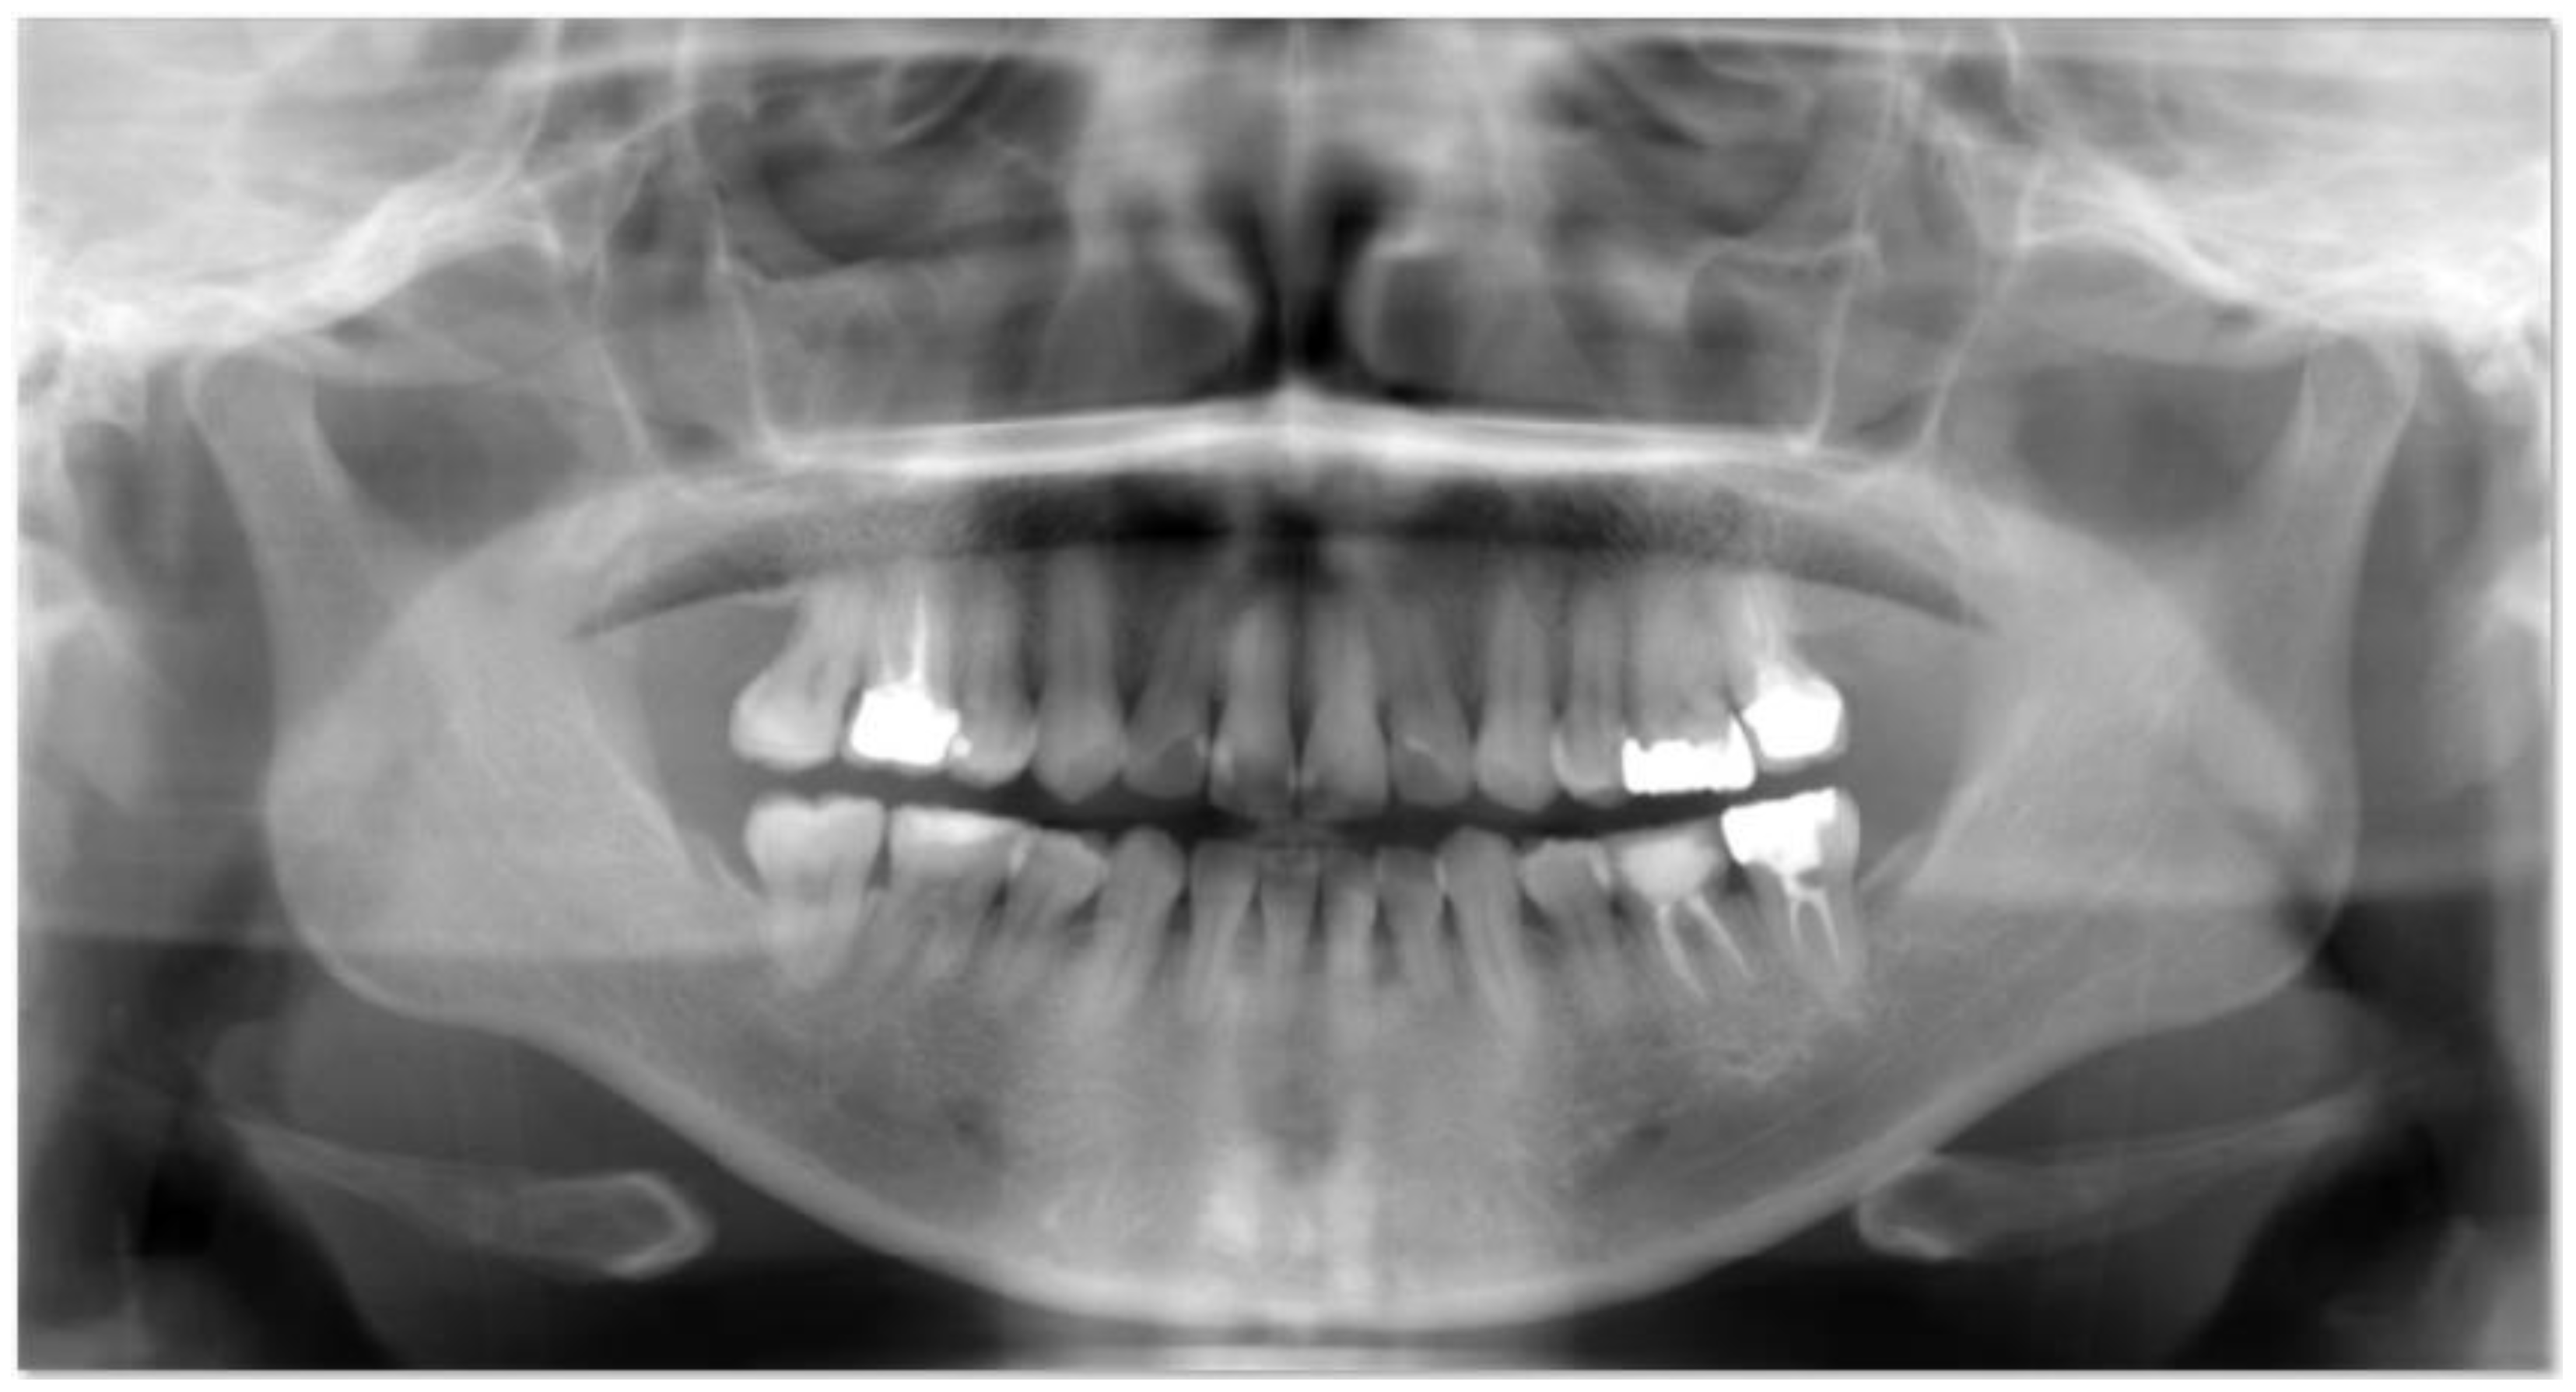

We received a dataset from dentists at Shinjuku East Dental Office. The dataset consists of unprocessed radiographs of 95 individuals. These radiographs were automatically processed to generate 533 tooth regions in the tooth region proposal stage. Images are from real patient cases from the hospital. The patients were 18 years old or older and provided consent. It is important to highlight that caries is more severe in adults (over 18 years old) since their teeth are no longer milk teeth but rather permanent teeth, which cannot be restored to their previous state. The University Committee at Tokai evaluated the publishing and usage rights of the images in the dataset based on ethical considerations. Figure 2 shows an example image from the dataset. It includes the mouth and a portion of the patient’s jaw bone.

Figure 2.

Panoramic radiographs.